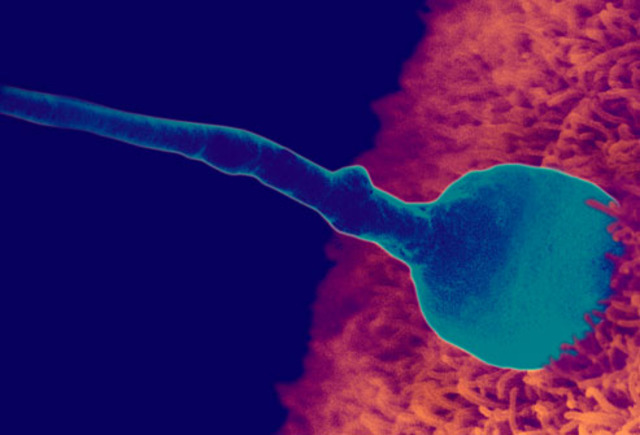

Prenatal Development- Fertilization

Fertilization is the process by which a sperm and an ovum-the male and female gametes- join to create a single-celled zygote.

This process takes about 24 hours and it only takes one sperm to fertilize an ovum, and each sperm and ovum contains all the genetic data necessary to produce a new human. Picture- www.webmd.com